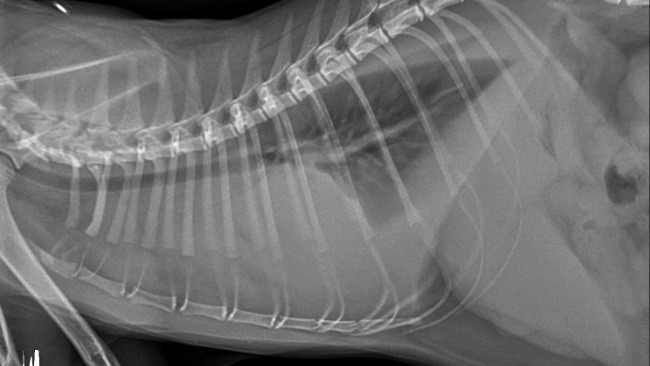

Ten drugi sprawił, że miałam płyn w klatce piersiowej i bardzo dusiłam się. Nie miałam czym oddychać.

Sporo tego płynu było, Pan Doktor mi go zabrał ale i tak czułam się źle i nie jadłam.

Gdy taki płyn jest przy płucach i one toną, to można podać Kotkom lek, który ratuje życie.